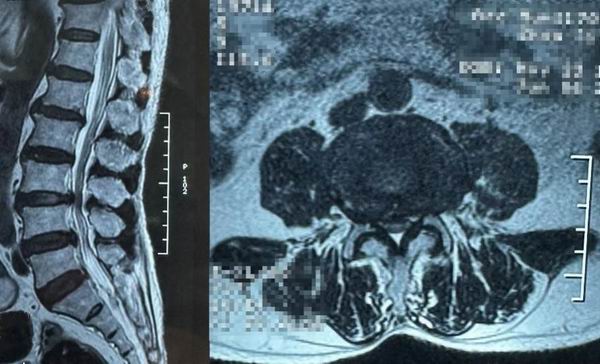

患者術(shù)前影像資料

患者男性,67歲,因“腰臀部疼痛伴雙下肢麻木半月余”入院。

診斷:L4-5節(jié)段腰椎間盤突出癥,伴腰椎椎管狹窄癥。

手術(shù)方案:顯微鏡輔助下椎間盤髓核摘除聯(lián)合纖維環(huán)縫合手術(shù)。